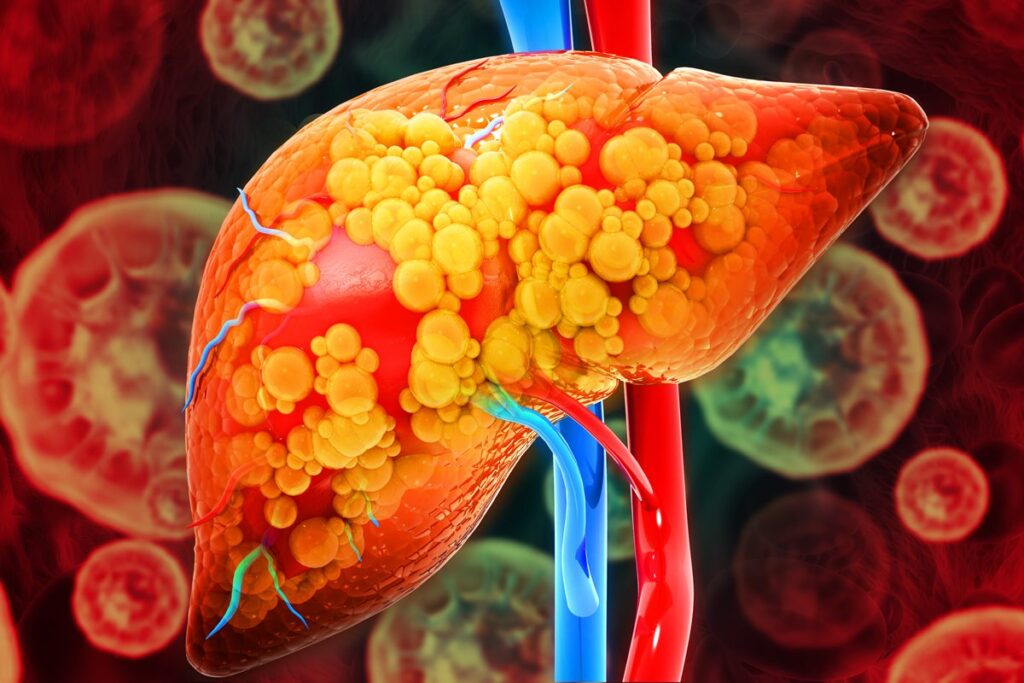

Algumas bebidas podem prejudicar o funcionamento do fígado

O órgão atua na filtragem do sangue

A condição de gordura no fígado acomete 30% da população mundial